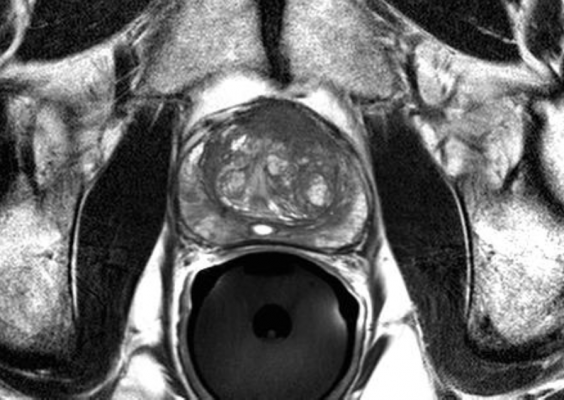

Under an exploratory investigational new drug, using a cross-over design, researchers compared the pharmacokinetics, biodistribution, and tumor uptake of Tc-99m MIP-1404 and Tc-99m MIP-1405 in 6 healthy men and 6 men with radiographic evidence of metastatic prostate cancer. Whole body images were obtained at 10 minutes and at 1, 2, 4 and 24 hours. SPECT was performed between 3 and 4 hours after injection. Prior to the study, no single target-specific Tc-99m radiopharmaceutical could image prostate cancer in soft tissue, lymph nodes and bone (bone metastasis) based on planar and SPECT. There was no uptake in degenerative bone disease, which often confounds bone scans.

“This research represents an innovative prostate cancer planar and SPECT imaging technology—addressing unmet clinical need for sensitive and selective imaging of loco-regional and distant metastatic prostate cancer,” stated Shankar Vallabhajosula, Ph.D., lead author of the study “99mTc-Labeled Small Molecule Inhibitors of Prostate Specific Membrane Antigen: Pharmacokinetics and Biodistribution Studies in Healthy Subjects and Patients with Metastatic Prostate Cancer. “With respect to imaging, the lack of focal uptake in the normal prostate of healthy volunteers with both compounds further demonstrated that PSMA is a viable targeting mechanism for detection and visualization of prostate cancer and suggests that this imaging approach is highly sensitive and disease specific.”

There was good correlation with bone scans in most subjects, although in general, more lesions were visualized with MIP-1404 and MIP-1405 than with bone scans, suggesting this agent may be more sensitive to detecting skeletal or marrow invasion earlier than bone scans. “We also demonstrated that Tc-99m MIP-1404 has favourable pharmacokinetics and biodistribution, which represents a breakthrough in imaging of prostate cancer for the following reasons: Tc-99m MIP-1404 can image prostate cancer in lymph nodes, soft tissue and bone,” noted Vallabhajosula.